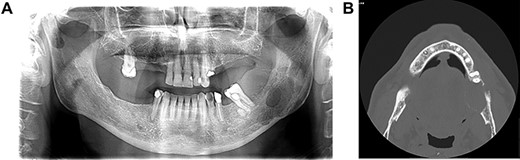

Panoramic radiogram and CT. A panoramic radiogram (A) and a CT (B) revealed the presence of a large and well-delineated radiolucency in the mandible.

Orthopantomography showed the presence of a large, round, well-circumscribed radiolucency in the mandible (Fig. 2A). A CT revealed an expansive lesion and a thinner cortical bone with partial interruption of the cortical margins. The mandibular canal was involved (Fig. 2B).